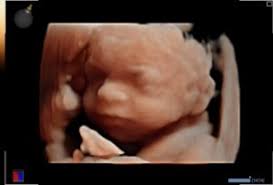

Pretecho - indien gewenst

Met een pretecho kun je een keertje extra naar je kindje kijken. Wij doen geen uitspraken over het geslacht van de baby. De pretecho wordt niet door de verzekeraar vergoed en is bedoeld voor cliënten van Sela. Je kunt hieronder meer informatie vinden over de kosten en pakketten voor pretecho’s die namens Sela Verloskundigen worden aangeboden. Of bel ons en maak direct een telefonische afspraak!